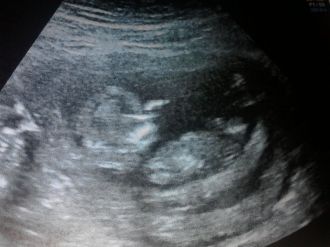

Oufff tout va bien je suis trop heureuse en fin je peux dire je suis enceinte!! avec le papa on a déja un pronostic pour le sexe je vous met une foto puis une otre aprè dites moi ce que vous en pensez!! donc la dpa est pour le 10 novembre!!après l'écho direction labo pour faire la pds pour la trisomie et les magasins pour acheter un petit truc je vous met aussi la foto ensuite!!